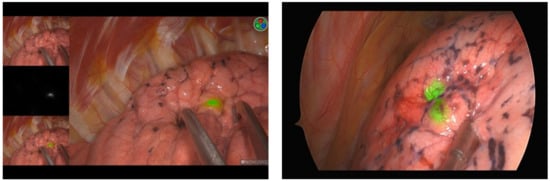

| Identification of the pleural tattoo, n (%) | 172 (98.3%) |